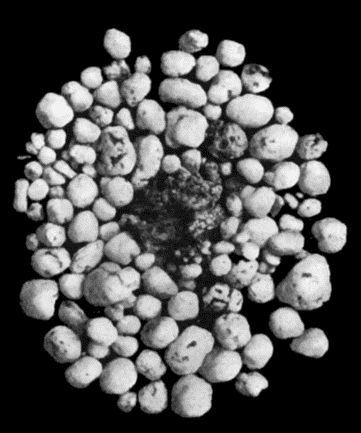

30.Colony of Actinomyces 126

31.Actinomycosis of Maxilla 128